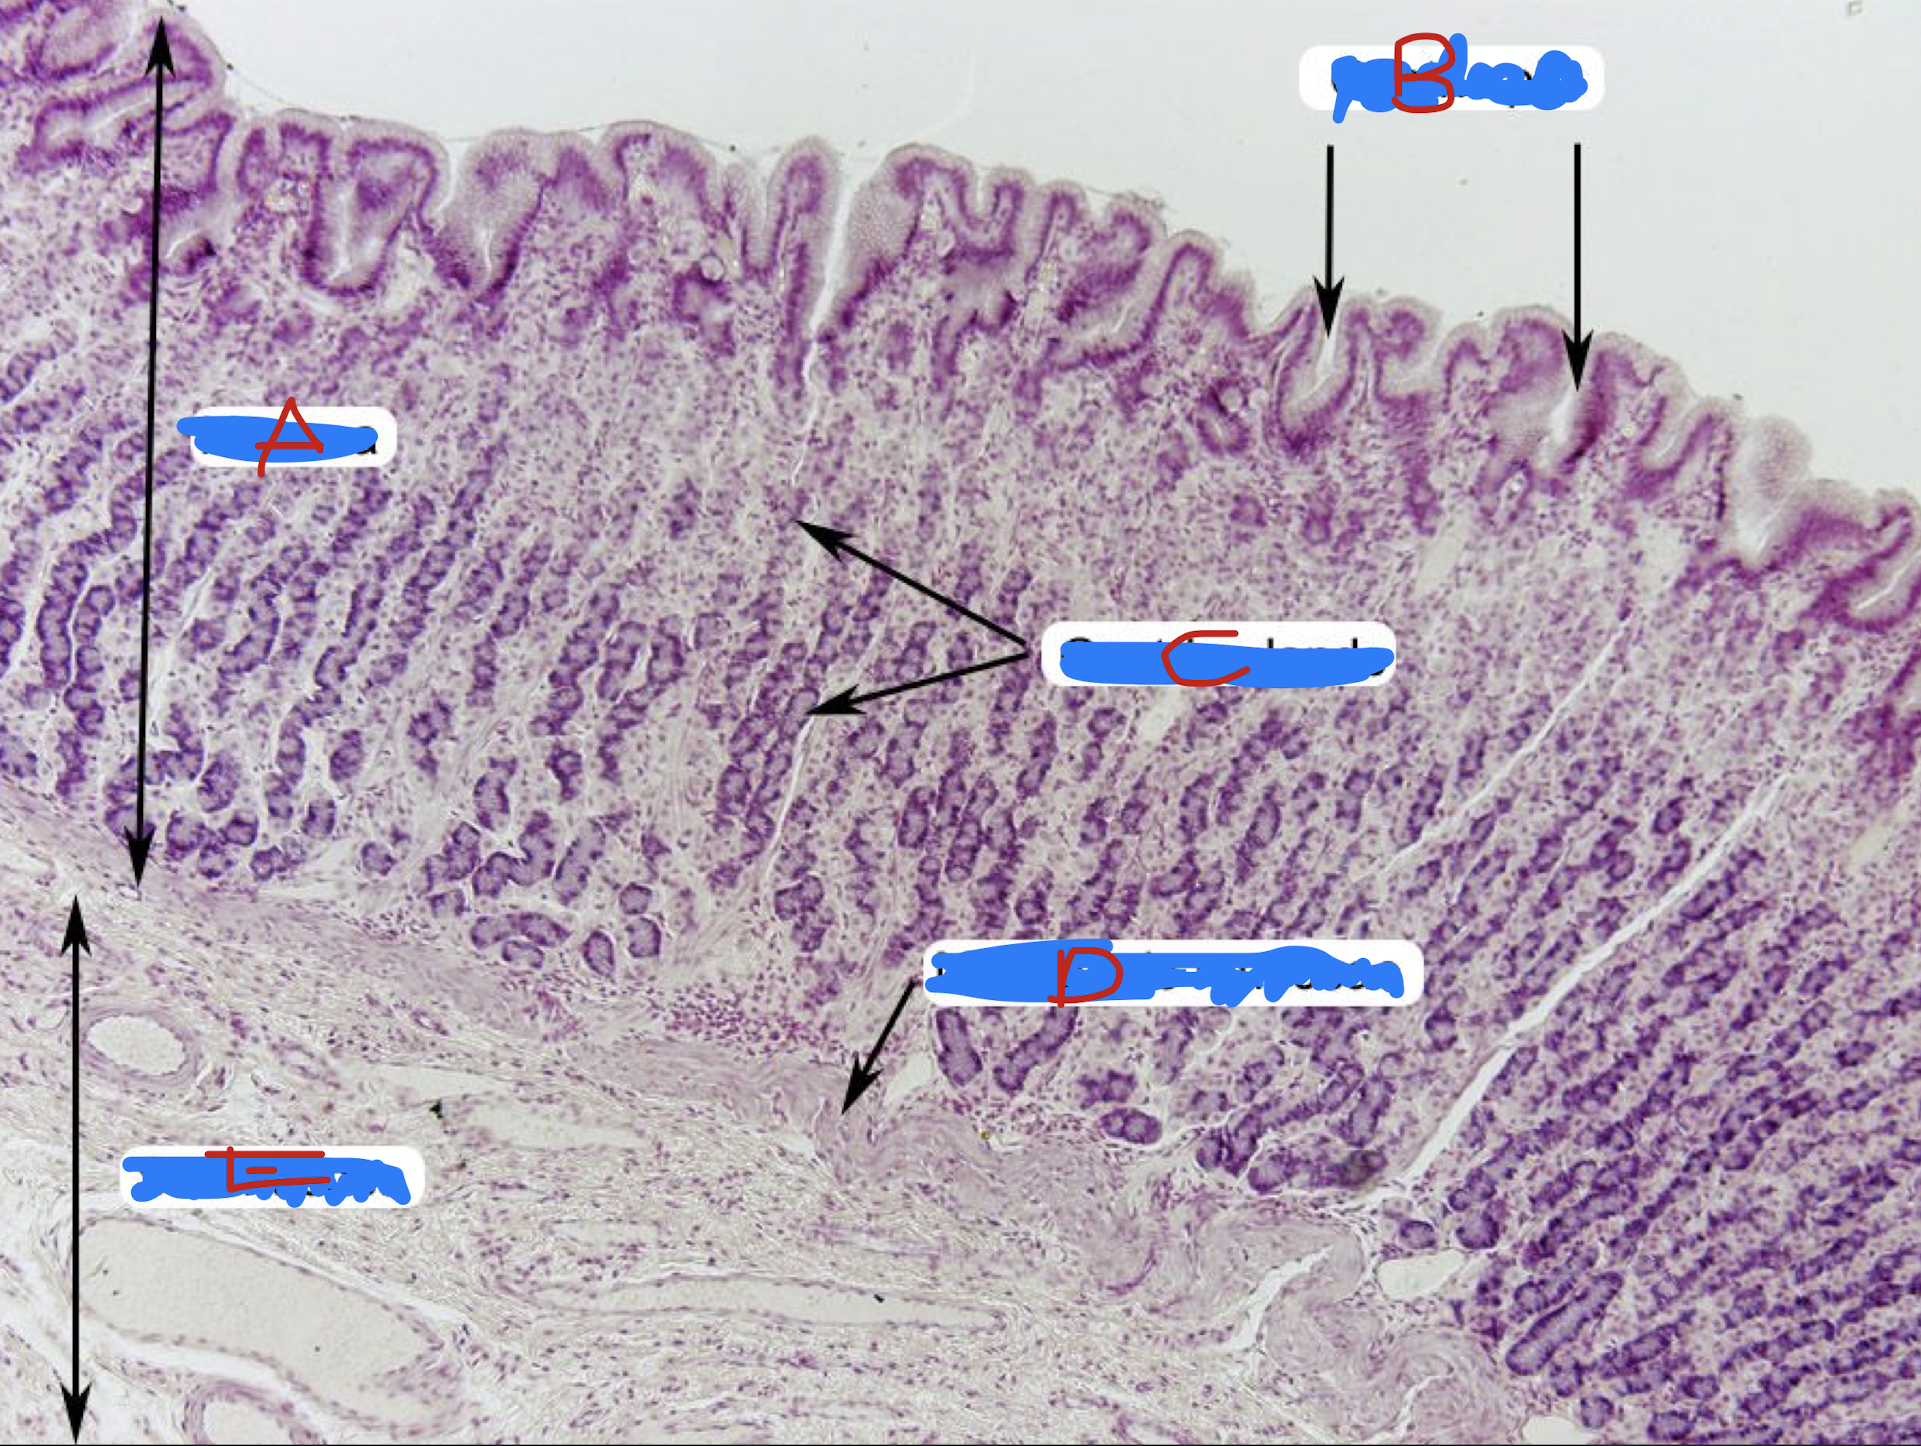

COLON

goblet cells

plenty of goblet cells in the intestinal gland

Identify the structure and its parenchyma

F: no more intestinal villi

T/F: The structure has intestinal villi

T

T/F: Crypts of Lieberkuhn are still present and usually longer and straighter than that of small intestine

intestinal glands with plenty of goblet cells

Identify the structure